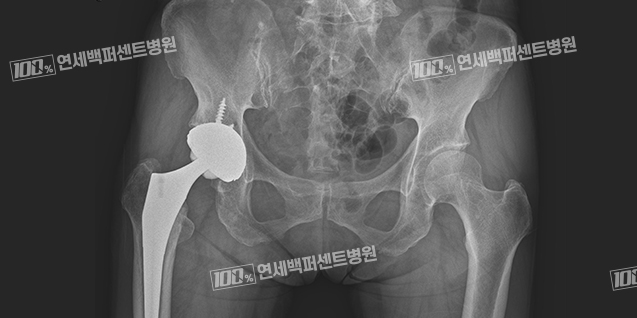

고관절 인공관절 치환술

골절의 정도가 심하거나 고령층에서 골절이 늦게 발견되었을 경우 뼈의 부러진 조각을

제거하고 고관절의 일부 또는 전부를 인공관절로 치환하는 수술을 진행

합니다.

고관절 골절 치료 Before & After

대퇴경부골절 치료 전

고관절 인공관절 치환술 후